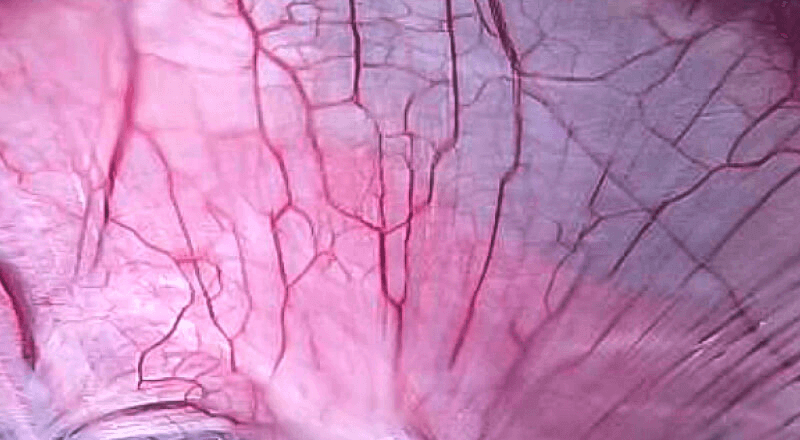

是一种基于血红蛋白对不同波长光吸收系数不同的原理而设计的智能染色成像系统,兼有电子染色和光学染色功能,能够凸显粘膜血管结构,有助于病灶部位识别和诊断,为临床医生术中判断提供参考信息。

血管对比度分布光谱曲线

VIST光谱

光电复合染色成像